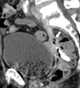

Air hose injury of rectum